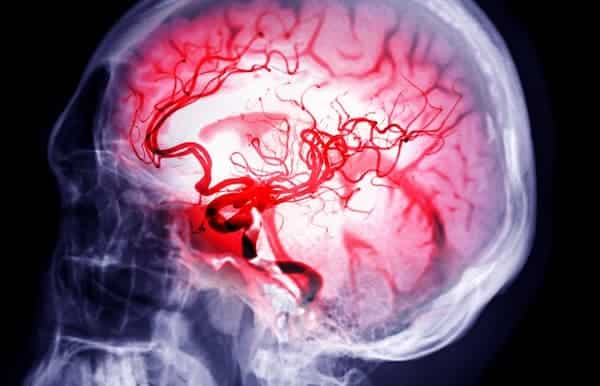

سکته مغزی زمانی رخ میدهد که جریان خون به بخشی از مغز قطع یا کاهش یابد و از رسیدن اکسیژن و مواد مغذی به بافت مغز جلوگیری شود. این وضعیت باعث مرگ سلولهای مغزی در عرض چند دقیقه میشود. سکته مغزی یک وضعیت اورژانسی است که نیازمند درمان فوری برای کاهش آسیب مغزی و عوارض است.

آنژیوگرام مغزی: نمایش دقیق رگهای خونی مغز.